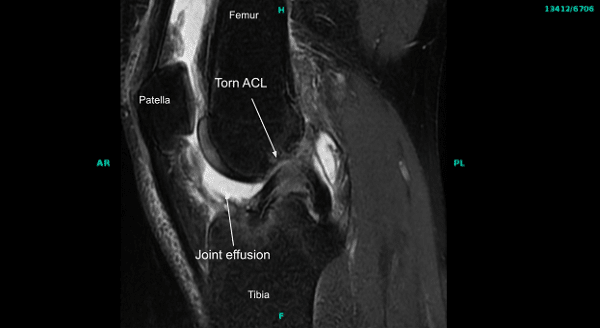

Physical examination was positive for ACL deficiency in the right knee. MRIs of the right knee joint confirmed the injury to ACL. No other pathology was seen. The patient had tried physical therapy in the past with no benefit.

MRI of the right knee joint